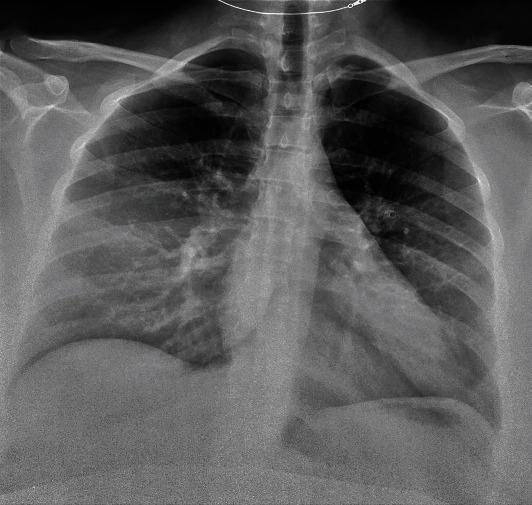

The rapidly expanding cases of the coronavirus disease 2019 (COVID-19) caused by the severe acute respiratory syndrome coronavirus 2 (SARS-CoV-2) have exposed vulnerable populations, including pregnant women to an unprecedented public health crisis. Recent data show that pregnancy in COVID-19 patients is associated with increased hospitalization, admission of the intensive care unit, and intubation. However, very few resources exist to guide the multidisciplinary team in managing critically ill pregnant women with COVID-19. We report our experience with managing a morbidly obese pregnant woman at 36 weeks' gestation with history of asthma and malignancy who presented with persistent respiratory symptoms at an outside hospital after being tested positive for SARS-CoV-2 polymerase chain reaction (PCR). Early in the course of the hospitalization, patient received remdesivir, convalescent plasma, bronchodilator, systemic steroids, and IV heparin for COVID-19 and concomitant asthma exacerbation and pulmonary embolism. Due to increasing oxygen requirements, she was eventually intubated and transferred to our institution for higher level of care. Respiratory acidosis, severe hypoxemia, and vent asynchrony were managed with vent setting adjustment and paralytics. After 12 hours from spontaneous rupture of her membranes and with stabilization of maternal status, patient underwent a term cesarean delivery for nonreassuring fetal heart tracing. The neonate was discharged on the 2 day of life, while the patient was extubated on the 6 postpartum day and was discharged to acute inpatient rehabilitation facility on the 19 hospital day. This report highlights the disease progression of COVID-19 in a pregnant woman, the clinical challenges in the critical care aspect of patient management, and the proposed multidisciplinary strategies utilizing an algorithmic approach to optimize maternal and neonatal outcomes.

由严重急性呼吸综合征冠状病毒2(SARS-CoV-2)引起的2019冠状病毒病(COVID-19)病例迅速增加,使包括孕妇在内的弱势群体面临前所未有的公共卫生危机。最近的数据显示,COVID-19患者怀孕与住院率增加、入住重症监护病房和插管有关。然而,几乎没有资源可指导多学科团队管理患有COVID-19的重症孕妇。我们报告了我们管理一名患有哮喘和恶性肿瘤病史、孕36周的病态肥胖孕妇的经验,该孕妇在SARS-CoV-2聚合酶链反应(PCR)检测呈阳性后,在外院出现持续呼吸道症状。在住院过程早期,患者因COVID-19以及伴随的哮喘加重和肺栓塞接受了瑞德西韦、康复期血浆、支气管扩张剂、全身用类固醇和静脉注射肝素治疗。由于氧需求增加,她最终插管并转至我院接受更高水平的治疗。通过调整通气设置和使用镇静剂处理呼吸性酸中毒、严重低氧血症和通气不同步。在胎膜自然破裂12小时后,随着母亲状况稳定,患者因胎儿心率监护不令人放心接受了足月剖宫产。新生儿出生后第2天出院,而患者产后第6天拔管,住院第19天出院至急性住院康复机构。本报告强调了COVID-19在孕妇中的疾病进展、患者管理重症监护方面的临床挑战,以及提出的利用算法方法优化母婴结局的多学科策略。